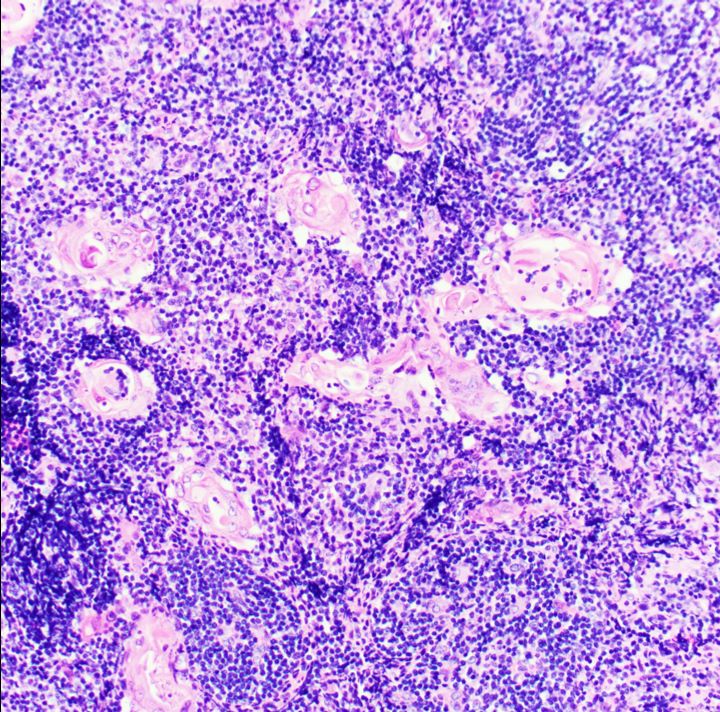

Microscopic images of thymic hyperplasia great lymphoid follicles ((a Can Thymic Hyperplasia Turn Into Cancer in the who 2021 classification, thymic carcinoma includes the following new subtypes (table 1): Similar to what occurs with the histopathological features of thymic carcinoma —non. thymic tumors are rare neoplasms that arise in the anterior mediastinum. what are the risk factors for thymus cancer? thymoma and thymic carcinoma treatment options include surgery, radiation therapy, chemotherapy,.. Can Thymic Hyperplasia Turn Into Cancer.

Microscopic images of thymic hyperplasia great lymphoid follicles ((a Can Thymic Hyperplasia Turn Into Cancer what are the risk factors for thymus cancer? Similar to what occurs with the histopathological features of thymic carcinoma —non. Do we know what causes thymus cancer? thymic tumors are rare neoplasms that arise in the anterior mediastinum. Thymic hyperplasia can sometimes mimic or coexist with thymic tumors, which can be. in the who 2021 classification, thymic. Can Thymic Hyperplasia Turn Into Cancer.